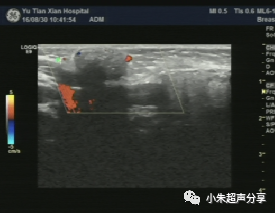

病例6  男,8岁,头顶毛母质瘤,血流丰富